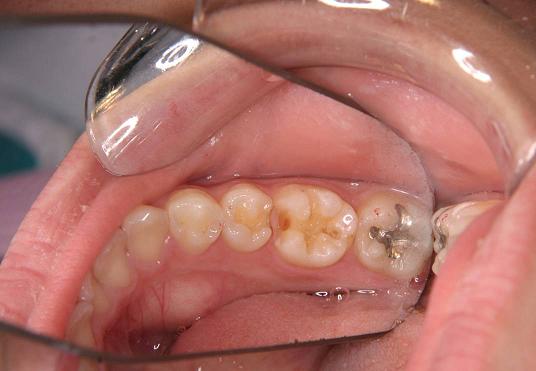

【症例 1】左下5・6番(一部分)2本 (18才,女性)

奥歯の歯の間が2本虫歯で

歯を削った後です

(ミラー像)

2.グラディア2本をつけました